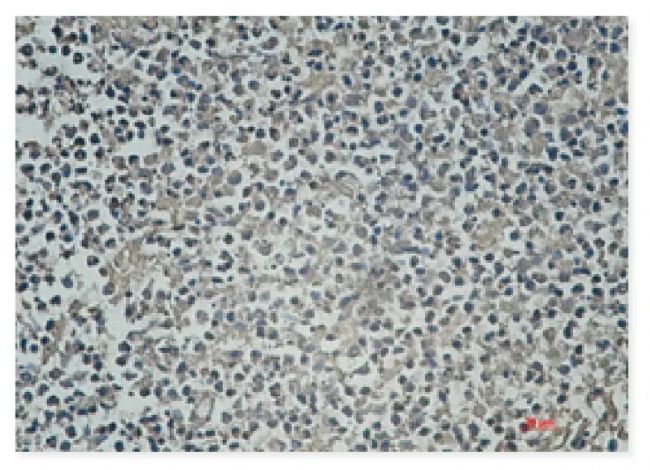

應(yīng)用:WB, IP, IHC-P

反應(yīng)物種:Human, Mouse, Rat

IHC-P analysis of paraffin-

embedded human lung cancer

tissue using HDAC4 (A5)

Mouse mAb